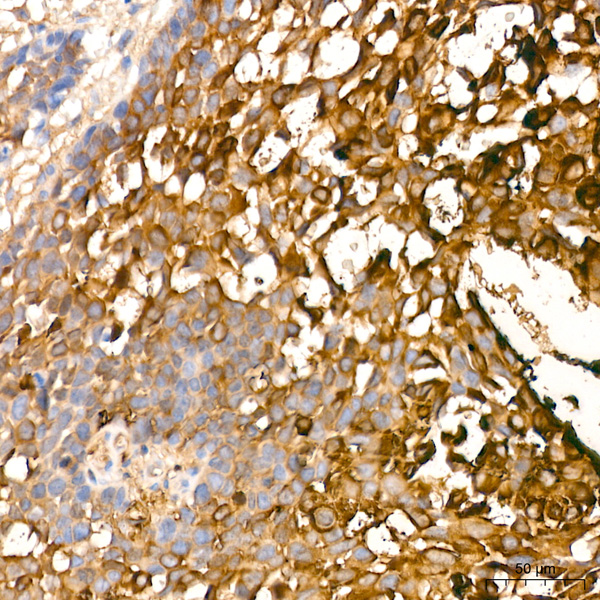

IHC (Immunohistochemisry)

(Immunohistochemistry analysis of paraffin-embedded Human lung squamous carcinoma tissue using Involucrin Rabbit mAb (AAA282636) at dilution of 1:100 (40x lens). Microwave antigen retrieval performed with 0.01M Tris/EDTA Buffer (pH 9.0) prior to IHC staining.)